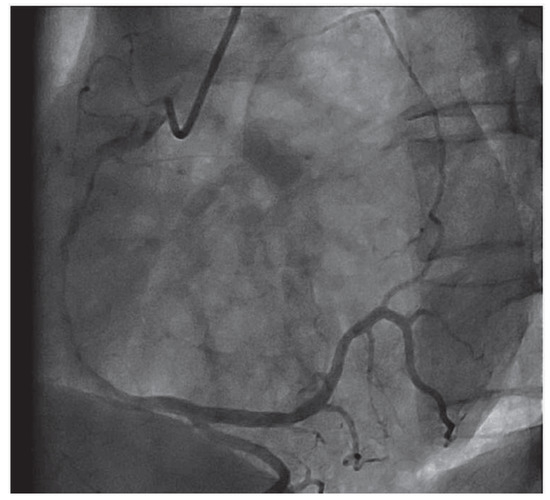

An 83-year-old man with ischaemic heart disease and a triple bypass in 2007 presented to the emergency department with increasing shortness of breath and weight gain of 5 kg over one month [...]